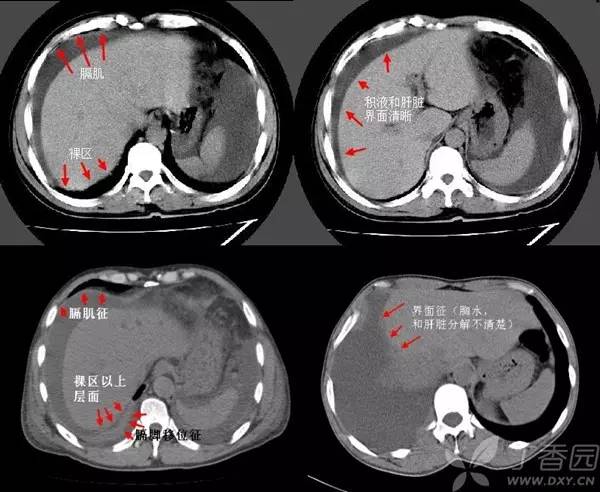

1. 膈肌征:横隔顶向头侧凸出,低密度影在膈外周为胸水,在膈内为腹水。

2. 膈脚移位征:胸水时压迫膈脚向前、向外侧移位。

3. 界面征:肝与肺在层面上的分界一般是清晰的,腹水时也清晰明确,而当胸水时则肝肺分界不清晰。

4. 肝裸区征:肝的背侧内部肝与膈肌直接相贴,此为裸区,产生腹水时液体不在此区潴留。